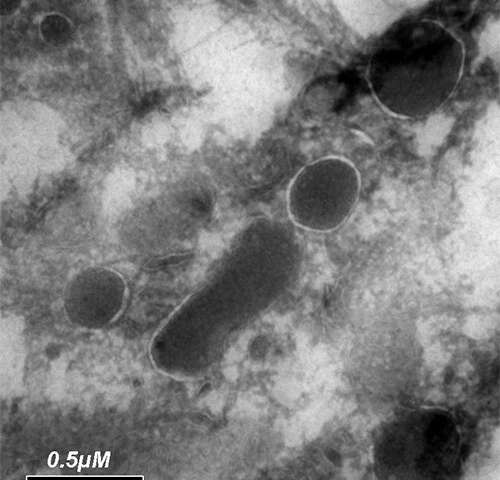

Immagine: questa immagine al microscopio elettronico rivela i batteri che vivono in una cellula tumorale. Credito: Weizmann Institute of Science.

Alla fine, il team ha prodotto uno studio dettagliato che descrive, ad alta risoluzione, i batteri che vivono in questi tumori: cervello, ossa, mammella, polmone, ovaio, pancreas, colon-retto e melanoma. I ricercatori hanno scoperto che ogni singolo tipo di cancro, dal cervello all’osso, ospitano batteri e che diversi tipi di cancro ospitano diverse specie di batteri. I tumori al seno, tuttavia, presentavano il maggior numero e maggiore diversità di batteri. Il team ha dimostrato che è possibile trovare molti più batteri nei tumori della mammella rispetto al normale tessuto mammario che circonda questi tumori e che alcuni batteri sono stati trovati preferibilmente nel tessuto tumorale piuttosto che nel normale tessuto che li circonda. Per arrivare a questi risultati, il team ha dovuto superare diverse sfide. Per prima cosa, la massa di batteri in un campione di tumore è relativamente piccola, e i ricercatori hanno dovuto trovare il modo di concentrarsi su queste minuscole cellule all’interno delle cellule. Hanno anche dovuto eliminare ogni possibile contaminazione esterna. A tal fine, hanno utilizzato centinaia di controlli negativi e creato una serie di filtri computazionali per rimuovere le tracce di eventuali batteri che potrebbero provenire dall’esterno dei campioni di tumore. Il team è stato in grado di coltivare batteri direttamente dai tumori al seno umani e i loro risultati hanno dimostrato che i batteri trovati in questi tumori sono vivi. La visualizzazione al microscopio elettronico di questi batteri ha dimostrato che preferiscono annidarsi in una posizione specifica all’interno delle cellule tumorali, vicino al nucleo cellulare.